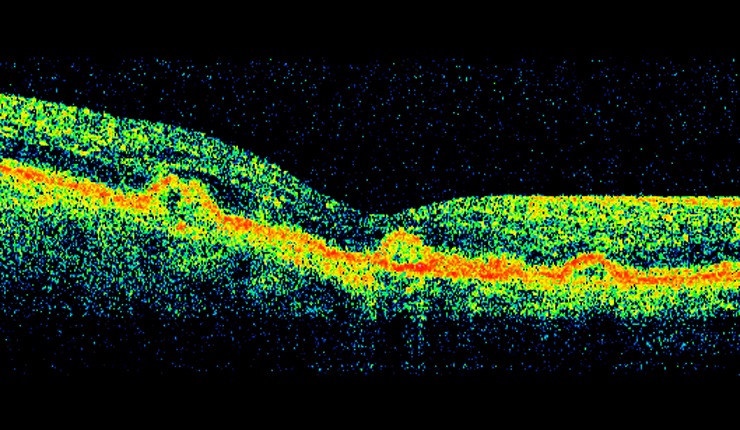

Highly reflective choroidal neovascular membrane (CNV) associated with AMD. Some residual fluid remaining at the interface of the CNV and outer retina.